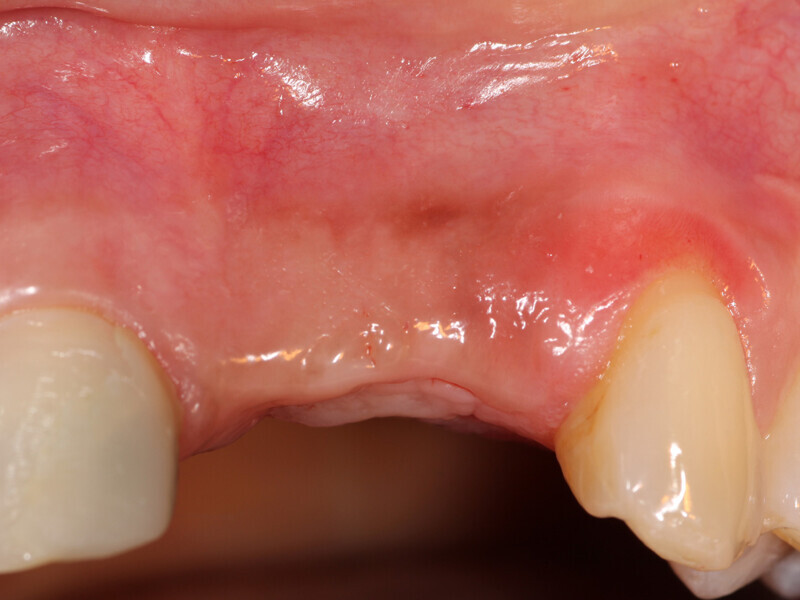

Fig. 15a: The previously deficient ridge at the left central and lateral incisors resulting from resorption following the previously extracted teeth had been augmented and is ready for implant placement following 4.5 months of graft healing.

Fig. 15b: The previously deficient ridge at the left central and lateral incisors resulting from resorption following the previously extracted teeth had been augmented and is ready for implant placement following 4.5 months of graft healing.